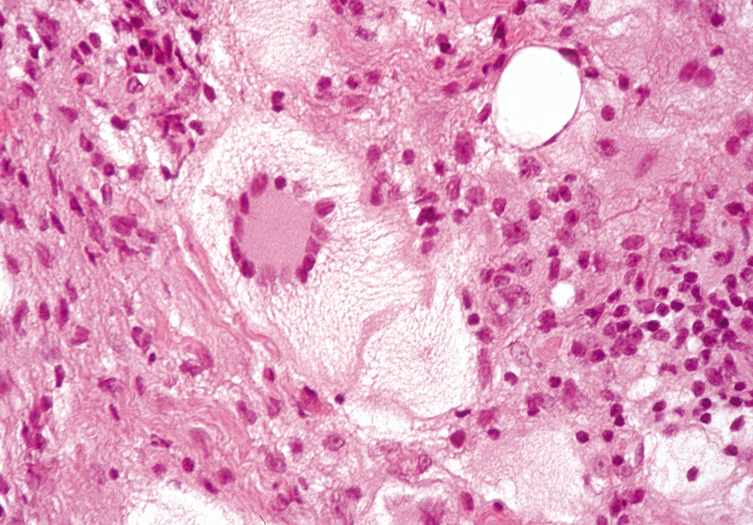

The architectural appearance is the most distinctive feature of the lesion for the histologic diagnosis of keratoacanthoma, which is made on low power or scanning magnification. There is a cup-shaped invagination of the epidermis filled with horny material. At the base of the crater, there is a bulbous proliferation of squamous epithelium showing abundant eosinophilic, glassy cytoplasm with little nuclear atypia. A few dyskeratotic cells may be seen, and mitotic figures may be present. There is often an inflammatory infiltrate containing lymphoid cells and eosinophils surrounding the epithelial proliferation (Fig. 47).

Fig. 47. Keratoacanthoma—A. Crater-shaped skin lesion filled with keratin. Parakeratosis and inflammation near the base of the lesion are common. These tumors may grow rapidly and may be confused microscopically with squamous cell carcinoma (hematoxylin and eosin stain). B. Clinical photograph of keratoacanthoma. (Photos courtesy of William Morris, M.D.)